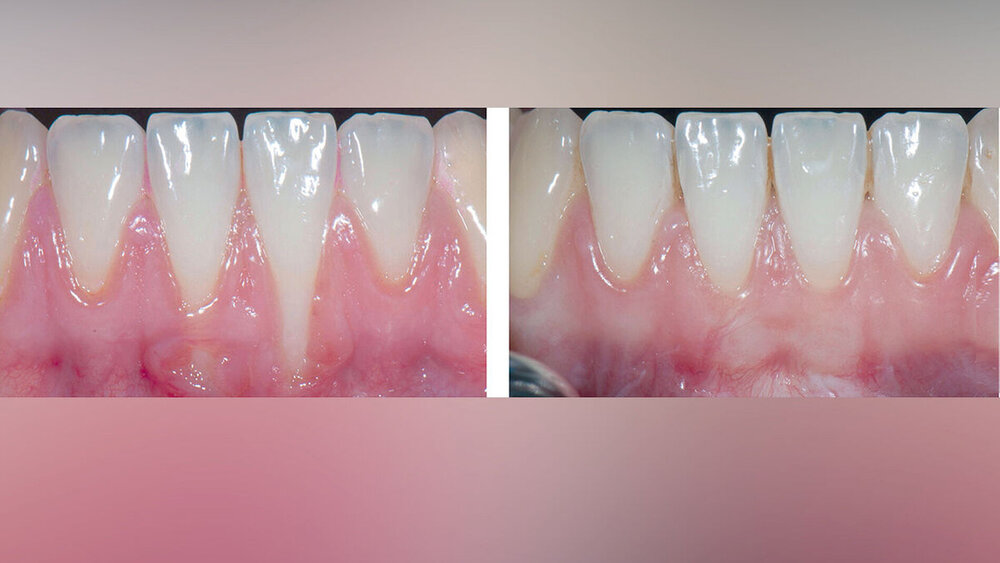

Rezessionsdeckung: Zur chirurgischen Therapie singulärer und multipler Rezessionen ist eine Vielzahl von Techniken entwickelt und in randomisierten Studien (RCTs) untersucht worden. Darauf basierende systematische Übersichten – häufig mit Metaanalysen – sind in den vergangenen 20 Jahren vielfach angefertigt worden, um immer wieder aktuelle Studien berücksichtigen zu können. Dabei konnte überzeugend demonstriert werden, dass mit einigen Techniken vorhersagbar sehr gute Ergebnisse erzielt werden können [Cairo et al., 2014; Graziani et al., 2014; Tonetti & Jepsen, 2014; Chambrone & Tatakis, 2015; Chambrone et al., 2018; 2019]. In den meisten RCTs wurde der Koronale Verschieblappen (KVL) allein oder aber im Vergleich zu KVL plus Bindegewebstransplantat (BGT), ADM, XCM oder Emdogain (EMD) untersucht.

Alle untersuchten chirurgischen Verfahren können bei singulären Rezessionen der Miller-Klassen I und II zu einem signifikanten Rückgang der Rezessionstiefe und einem klinischen Attachmentgewinn führen, ohne dass sich die Sonderungstiefen vergrößern. Dies gilt ebenfalls für multiple Rezessionen, allerdings ist die Datenlage dafür deutlich eingeschränkter.

Techniken, die BGT verwenden (mit KVL oder Tunnel) zeigen im Vergleich die besten Ergebnisse hinsichtlich mittlerer und kompletter Rezessionsdeckung und zugleich einer Verbreiterung des keratinisierten Gewebes.

Bei der Interpretation dieser sehr positiven Ergebnisse ist allerdings zu beachten, dass die allermeisten Studien nur Rezessionen ohne interdentalen Attachmentverlust (Miller-Klassen I und II, Cairo-Klasse RT1) eingeschlossen haben (Abbildungen 3 und 4).

Hinsichtlich einer Modifikation des Phänotyps kann im Vergleich zum alleinigen KVL bei Verwendung von BGT beziehungsweise ADM mit einer signifikanten Verbreiterung der keratinisierten Gewebe und bei Verwendung von BGT, ADM und XCM auch mit einer Zunahme der Gingivadicke gerechnet werden. Dies ist ein wichtiger, ebenfalls erwünschter zusätzlicher Effekt der Rezessionsdeckung, der hinsichtlich der Langzeitstabilität der erzielten Ergebnisse eine wichtige Rolle spielen kann [Barootchi et al., 2020]. Aktuell liegen Langzeitergebnisse aus drei nicht randomisierten Studien vor, die Patienten über mindestens 20 Jahre nachverfolgt haben [Agudio et al., 2017; PiniPrato et al., 2018a,b]. Rezidive wurden nur in denjenigen Bereichen beobachtet, in denen weniger als 2 mm breite keratinisierte Gewebe vorlagen. In dieser Hinsicht scheinen mit BGT behandelte Bereiche Vorteile zu haben.